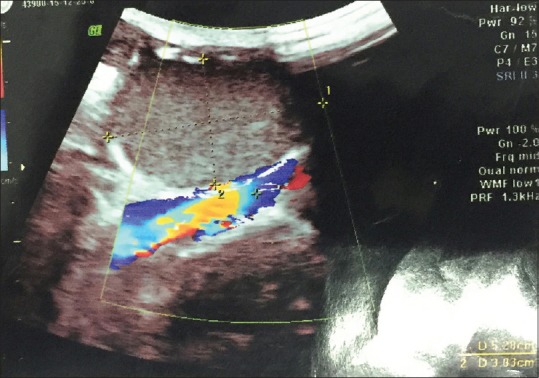

以腹股沟区肿块为表现的患者多怀疑为疝。表皮样囊肿常见于头颈部,很少由腹股沟管结构发展而来。我们在此报告一例罕见的表皮样囊肿,大小为7×8 cm,经超声诊断为腹股沟管的内容物。手术切除,病理证实为表皮样囊肿。我们的结论是,腹股沟区域的皮肤囊肿可能是一个表现,应该记住鉴别诊断。

The patients presenting with lump in inguinal area are mostly suspected as hernias. Epidermoid cyst commonly presenting in head and neck region rarely may develop from inguinal canal structures. We present here a rare case of epidermoid cyst measuring 7×8 cm as a content of inguinal canal diagnosed by ultrasonography. Surgical excision was done and confirmed as epidermoid cyst by histopathology. We conclude that cutaneous cysts in inguinal area may be a presentation and should be kept in mind for differential diagnosis.